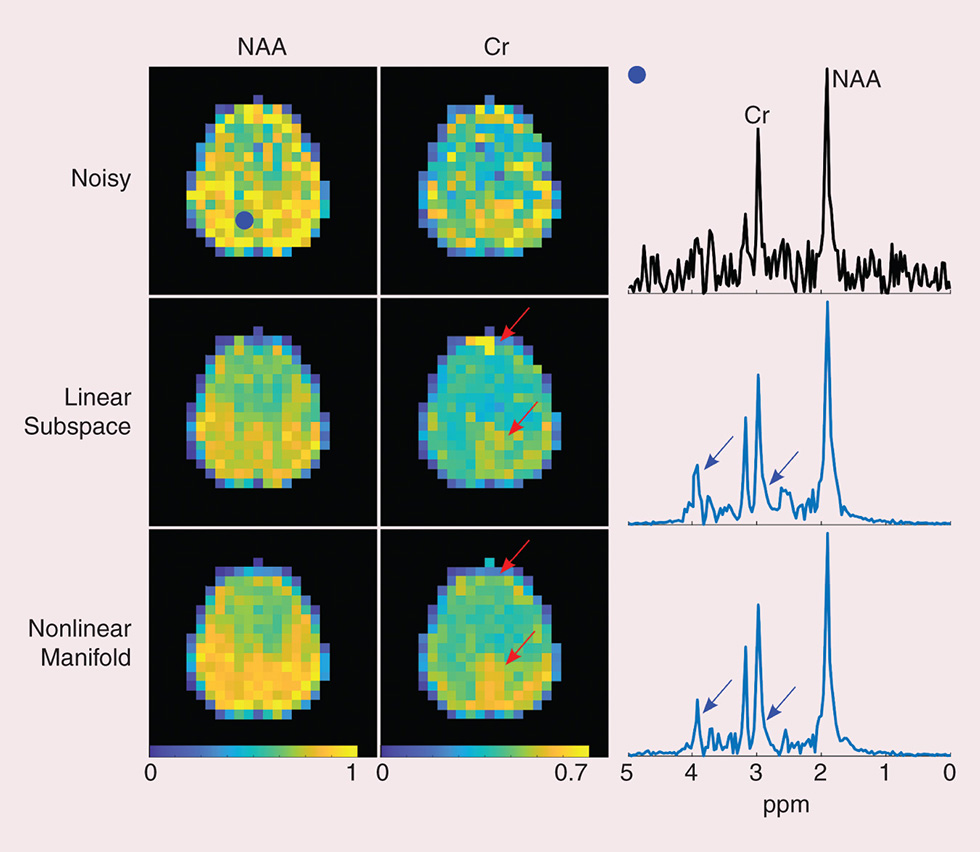

Retro Shooter G4 – Retro Shooter Light Gun Gaming, High-Dimensional MR Spatiospectral Imaging by Integrating,

High-Dimensional MR Spatiospectral Imaging by Integrating, High-Strain-Rate Compression Behavior of Ultrahigh